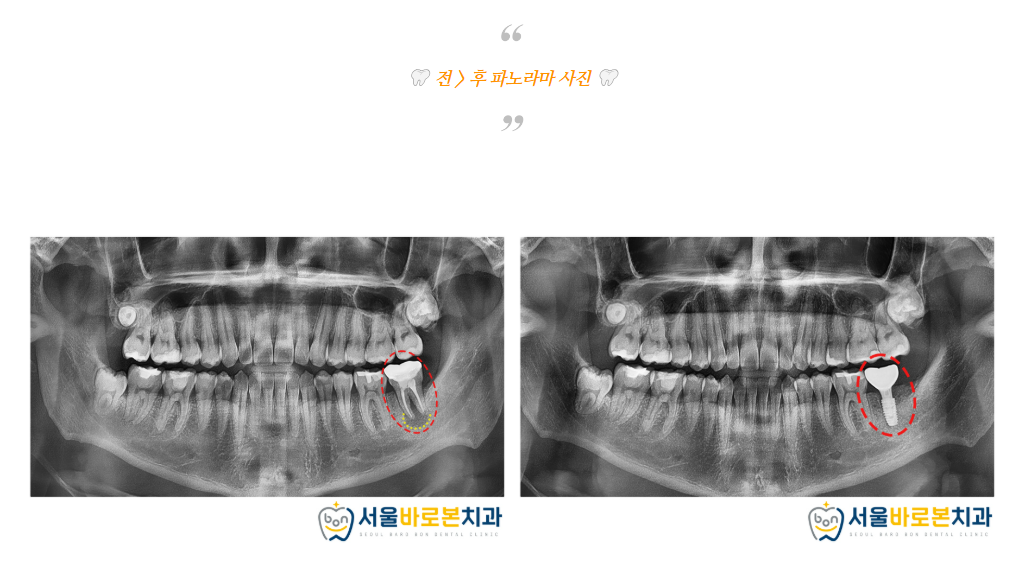

발치와 보존술로

뼈가 잘 회복된 것을 확인한 후

임플란트 수술을 도와드렸습니다.

현재는 치아 뿌리 역할을 하는

인공치근인 픽스처만 식립되어 있는 상태이고,

픽스처가 잇몸뼈에 잘 유착된 것을 확인한 후

치아 머리 역할을 하는 크라운(보철물)을 올려

치료를 마무리 하게 됩니다.

픽스처가 잇몸뼈에

잘 유착한것을 확인한 후

본뜨기 작업을 시행하고

크라운(보철물)을 끼워주었습니다.

치아 머리 역할을 하는

크라운(보철물)을 올리는

보철과정을 마무리 한 모습입니다. ^^